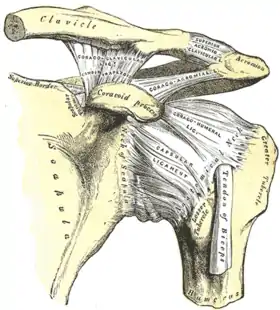

Capsule of shoulder-joint (distended). Anterior aspect. | |

The capsule is a soft tissue envelope that encircles the glenohumeral joint and attaches to the scapula, humerus, and head of the biceps. It is lined by a thin, smooth synovial membrane. This capsule is strengthened by the coracohumeral ligament which attaches the coracoid process of the scapula to the greater tubercle of the humerus. There are also three other ligaments attaching the lesser tubercle of the humerus to lateral scapula and are collectively called the glenohumeral ligaments.

The transverse humeral ligament, which passes from the lesser tubercle to the greater tubercle of humerus, covers the intertubercular groove, in which the long head of biceps brachii travels.